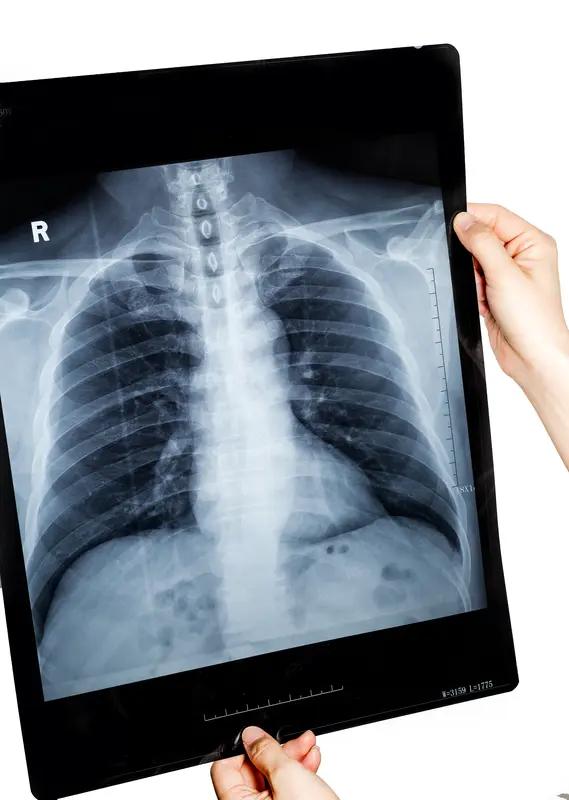

中老年体检,选对项目很重要,它们就是健康“守门人”。 胸部CT平扫(薄层扫描)得安排上,中老年是肺癌高发群体,早期肺癌没明显症状,普通胸片易漏小病变,薄层CT能精准识别几毫米的结节,早发现早干预。 13碳呼气试验也不能少,肠胃功能弱的中老年人适合做,吹口气就能检测幽门螺杆菌,这菌和胃炎、胃癌等有关。 颈部动脉彩超(8根血管)能评估血管情况,及时发现斑块和狭窄,预防脑梗中老年体检